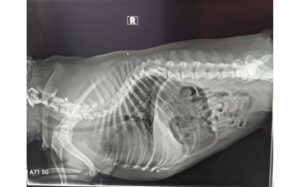

Chẩn đoán: chụp X-quang vùng ngực để phát hiện đốt sống dị dạng → dẫn đến liệt chi sau.

Biến dạng đốt sống ở Bull Pháp